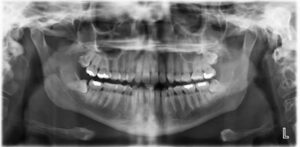

Panorex X-rays:

Panoramic X-rays offer a panoramic view of the entire mouth, including the teeth, jaws, sinuses, and surrounding structures. This comprehensive imaging technique is particularly useful for assessing overall dental health, planning orthodontic treatment, and evaluating the positioning of wisdom teeth.